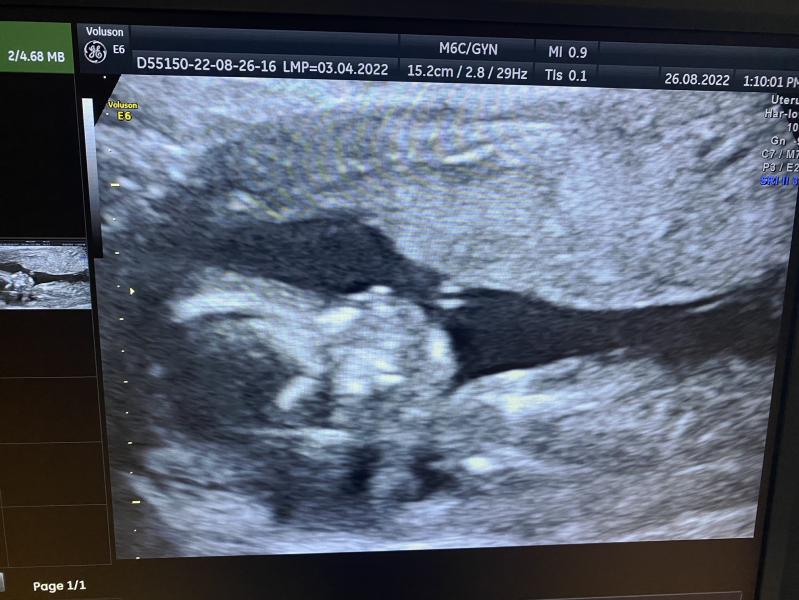

Скрининг 2 триместра: все хорошо! Пол ребенка подтвердили - будет мальчик, ура!

Сходила на 2 скрининг)) тьфу тьфу тьфу у нас все хорошо)) и подтвердили 100% мальчика!)☺️☺️☺️💞